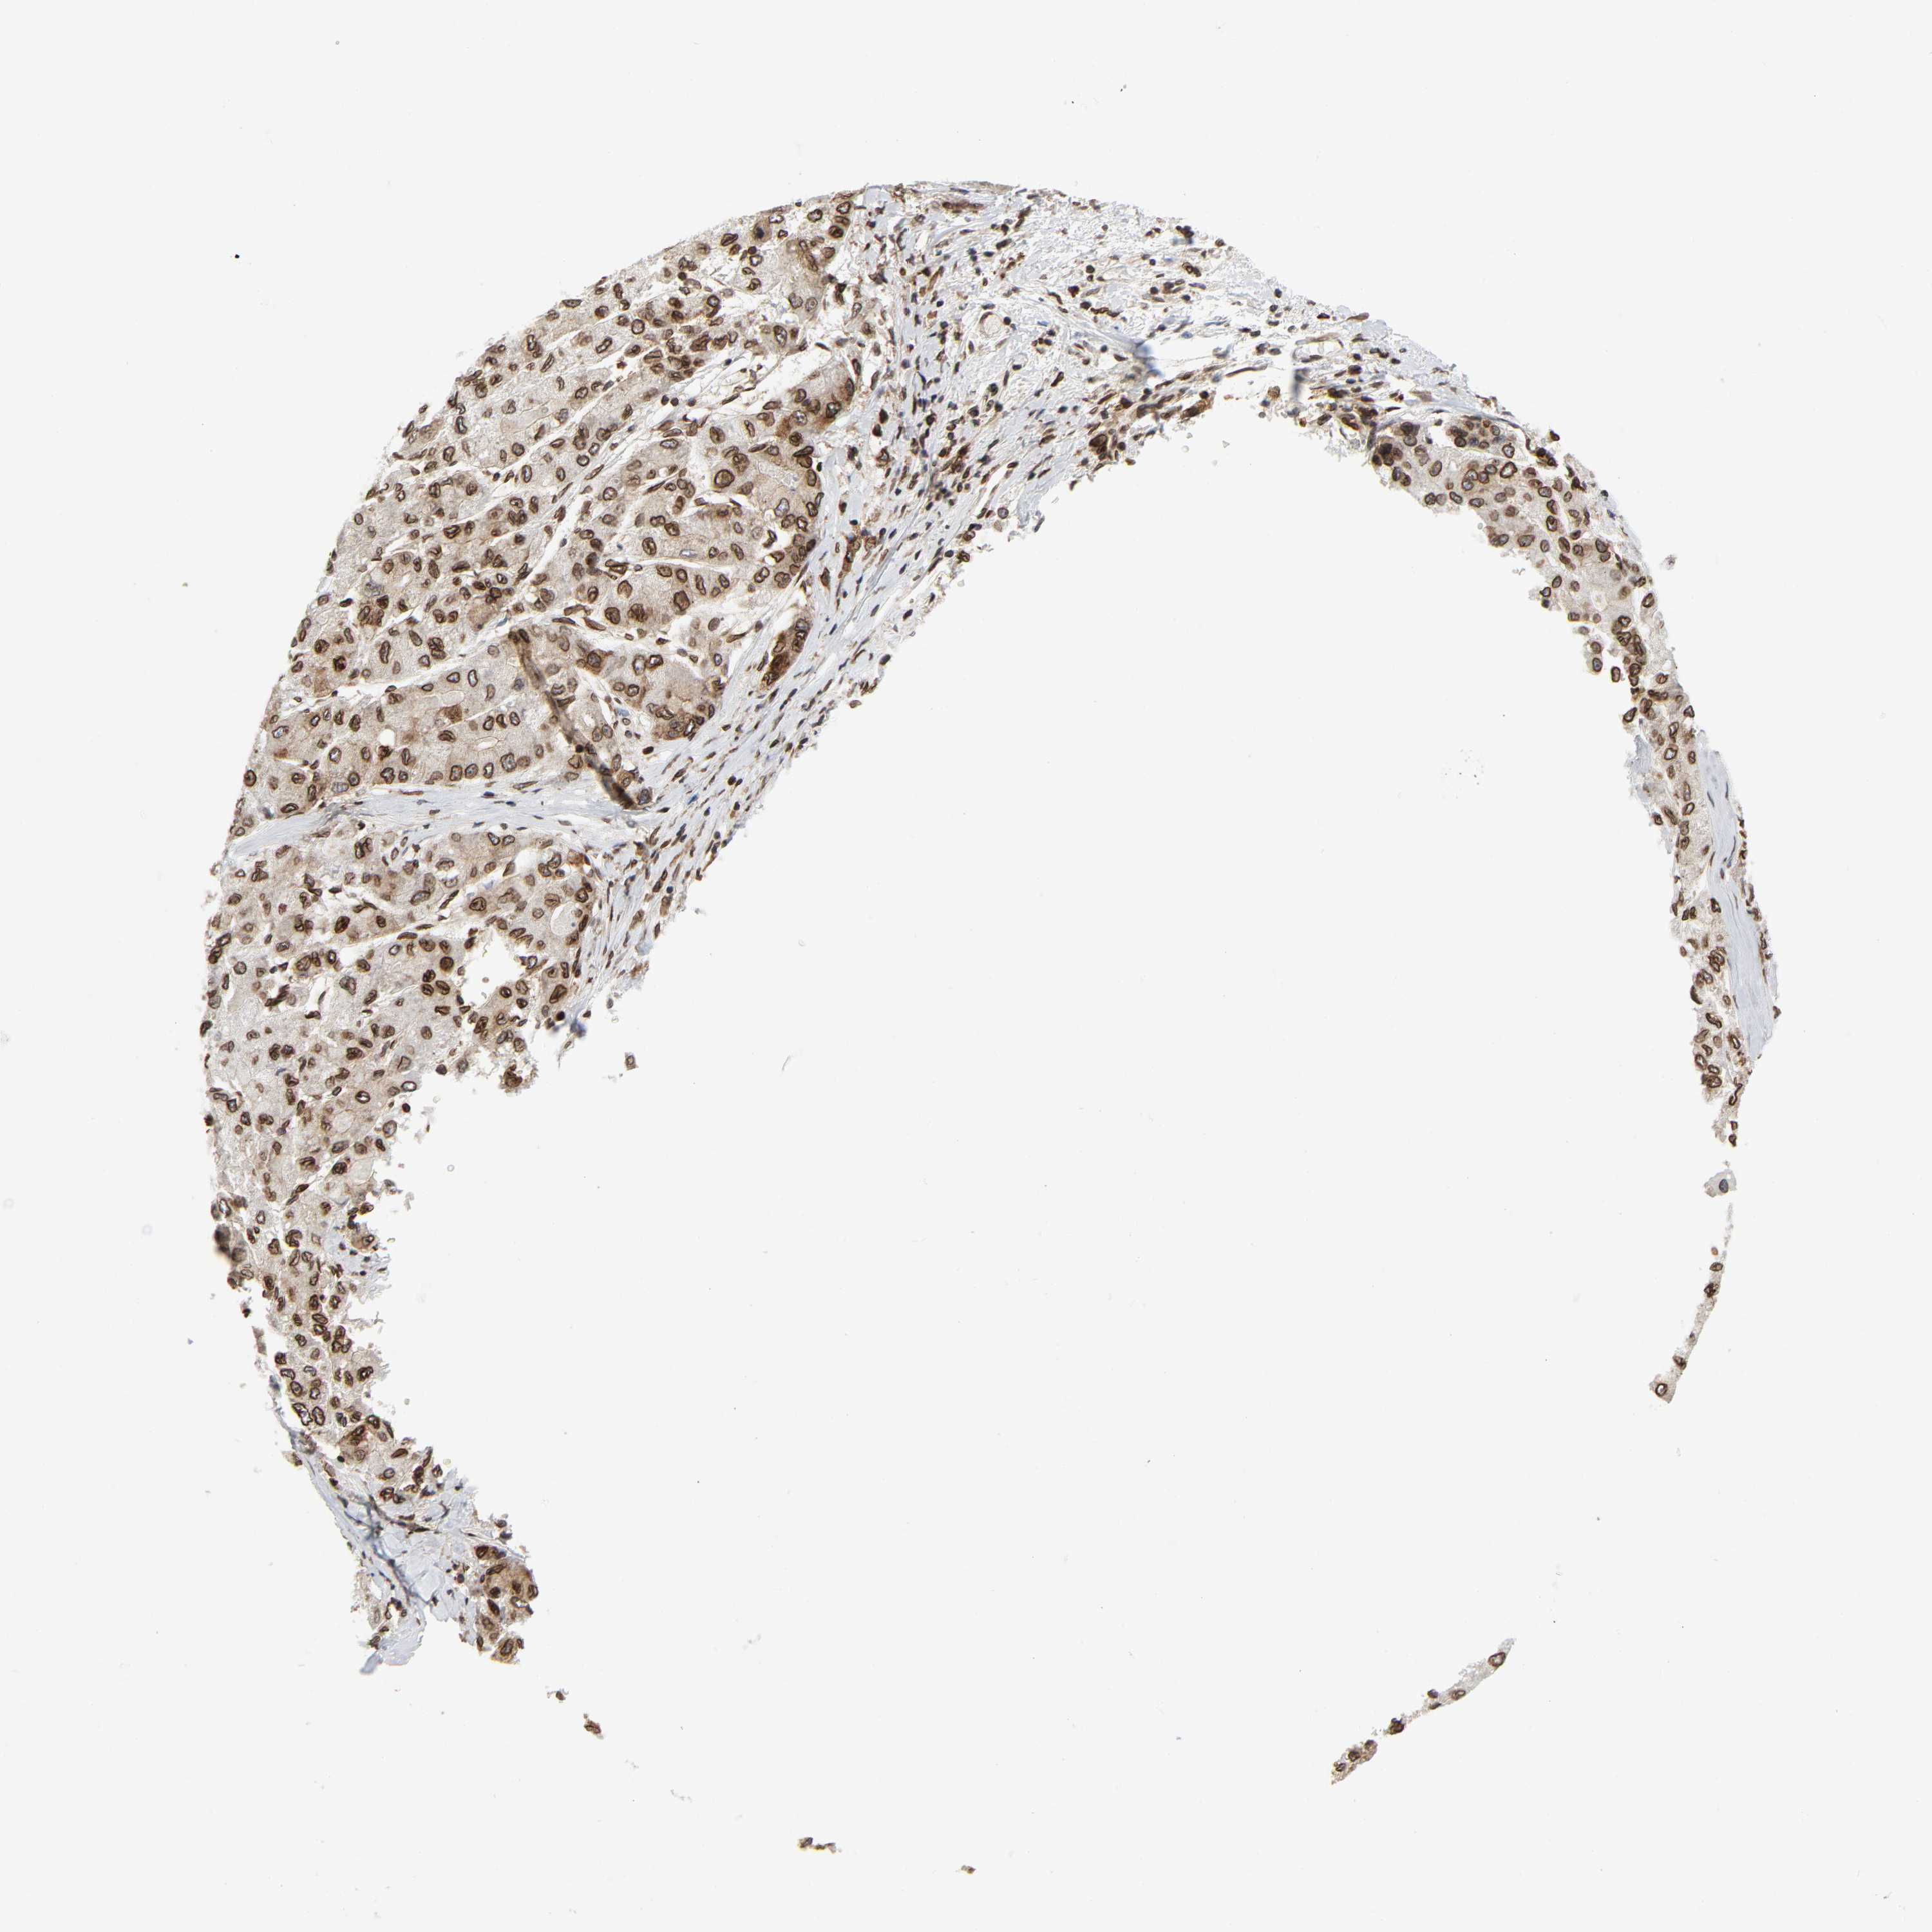

LIVER CANCER - Protein expressioni

A mouse-over function shows sample information and annotation data. Click on an image to view it in a full screen mode. Samples can be filtered based on level of antibody staining by selecting one or several of the following categories: high, medium, low and not detected. The assay and annotation is described here.

Note that samples used for immunohistochemistry by the Human Protein Atlas do not correspond to samples in the TCGA dataset.

Antibody stainingi

Antibody staining in the annotated cell types in the current human tissue is reported as not detected, low, medium, or high, based on conventional immunohistochemistry profiling in selected tissues. This score is based on the combination of the staining intensity and fraction of stained cells.

Each image is clickable and will lead to virtual microscopy that enables deeper exploration of all samples and also displays staining intensity scores, fraction scores and subcellular localization as well as patient and tissue information for each sample.

Antibody HPA050110

Antibody CAB004293

Staining

High

Medium

Low

Not detected

Intensity

Strong

Moderate

Weak

Negative

Quantity

>75%

75%-25%

<25%

None

Location

Nuclear

Cytoplasmic/membranous

Cytoplasmic/membranous,nuclear

Carcinoma, Hepatocellular, NOS

Cholangiocarcinoma